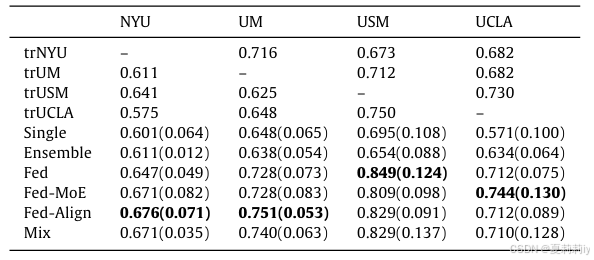

2.5.3. Comparisons with different strategies

①Evaluation methods:

②Comparison result: